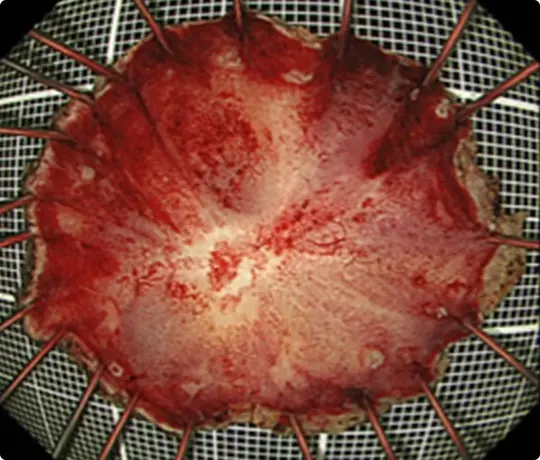

切除した検体をピンで伸ばして、ホルマリンで固定後、病理診断を行います。中央に見える赤く隆起している部分が腫瘍です(青い色素をかけています)。

病理診断で腫瘍は完全に切除されており、治癒と判定されました。